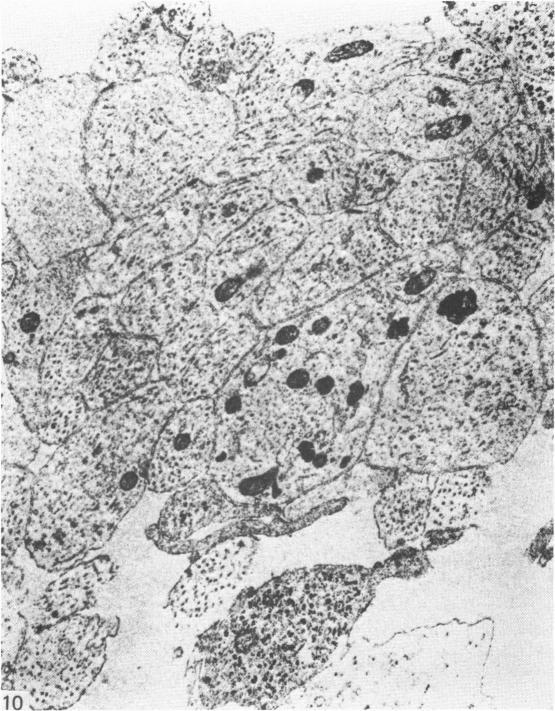

The concept that there are no nerves in the limb bud of mammalian embryos prior to differentiation has been re-examined. Rabbit embryos were collected at 260 and 290 hours gestation, which is prior to cartilage formation in the forelimb at 320 hours. Forelimb buds and adjacent neural tube were excised, fixed and embedded for light and electron microscopy. The limb buds were sectioned in two planes by serial 1 micrometer sections and inspected by light microscopy. Bundles of nerve fibres were seen within the proximal third of the limb bud, with distal ramification into adjacent zones of condensing mesenchyme. Electron microscopy confirmed the presence of axons and associated immature Schwann cells. These results demonstrate the existence of an anatomical framework through which a neurotrophic influence might be brought to bear upon mesenchyme prior to early differentiation.